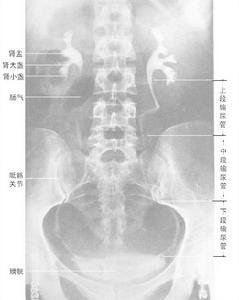

5.攝腹部(腎、膀胱)平片像,確定是否符合造影條件。

用於檢查泌尿道器質性病變,可觀察到尿路梗阻部位及原因;能顯示尿路結石造成的造影劑充盈缺損;對腎結核、慢性腎盂腎炎(CPN)、腎盂腫瘤所致的腎盂、腎盞破壞也各有其特徵性改變;此外,對腎實質腫瘤、囊性腎病、獨腎、腎下垂也有重要的診斷意義。對不便作膀胱鏡檢查的患者更為適用。